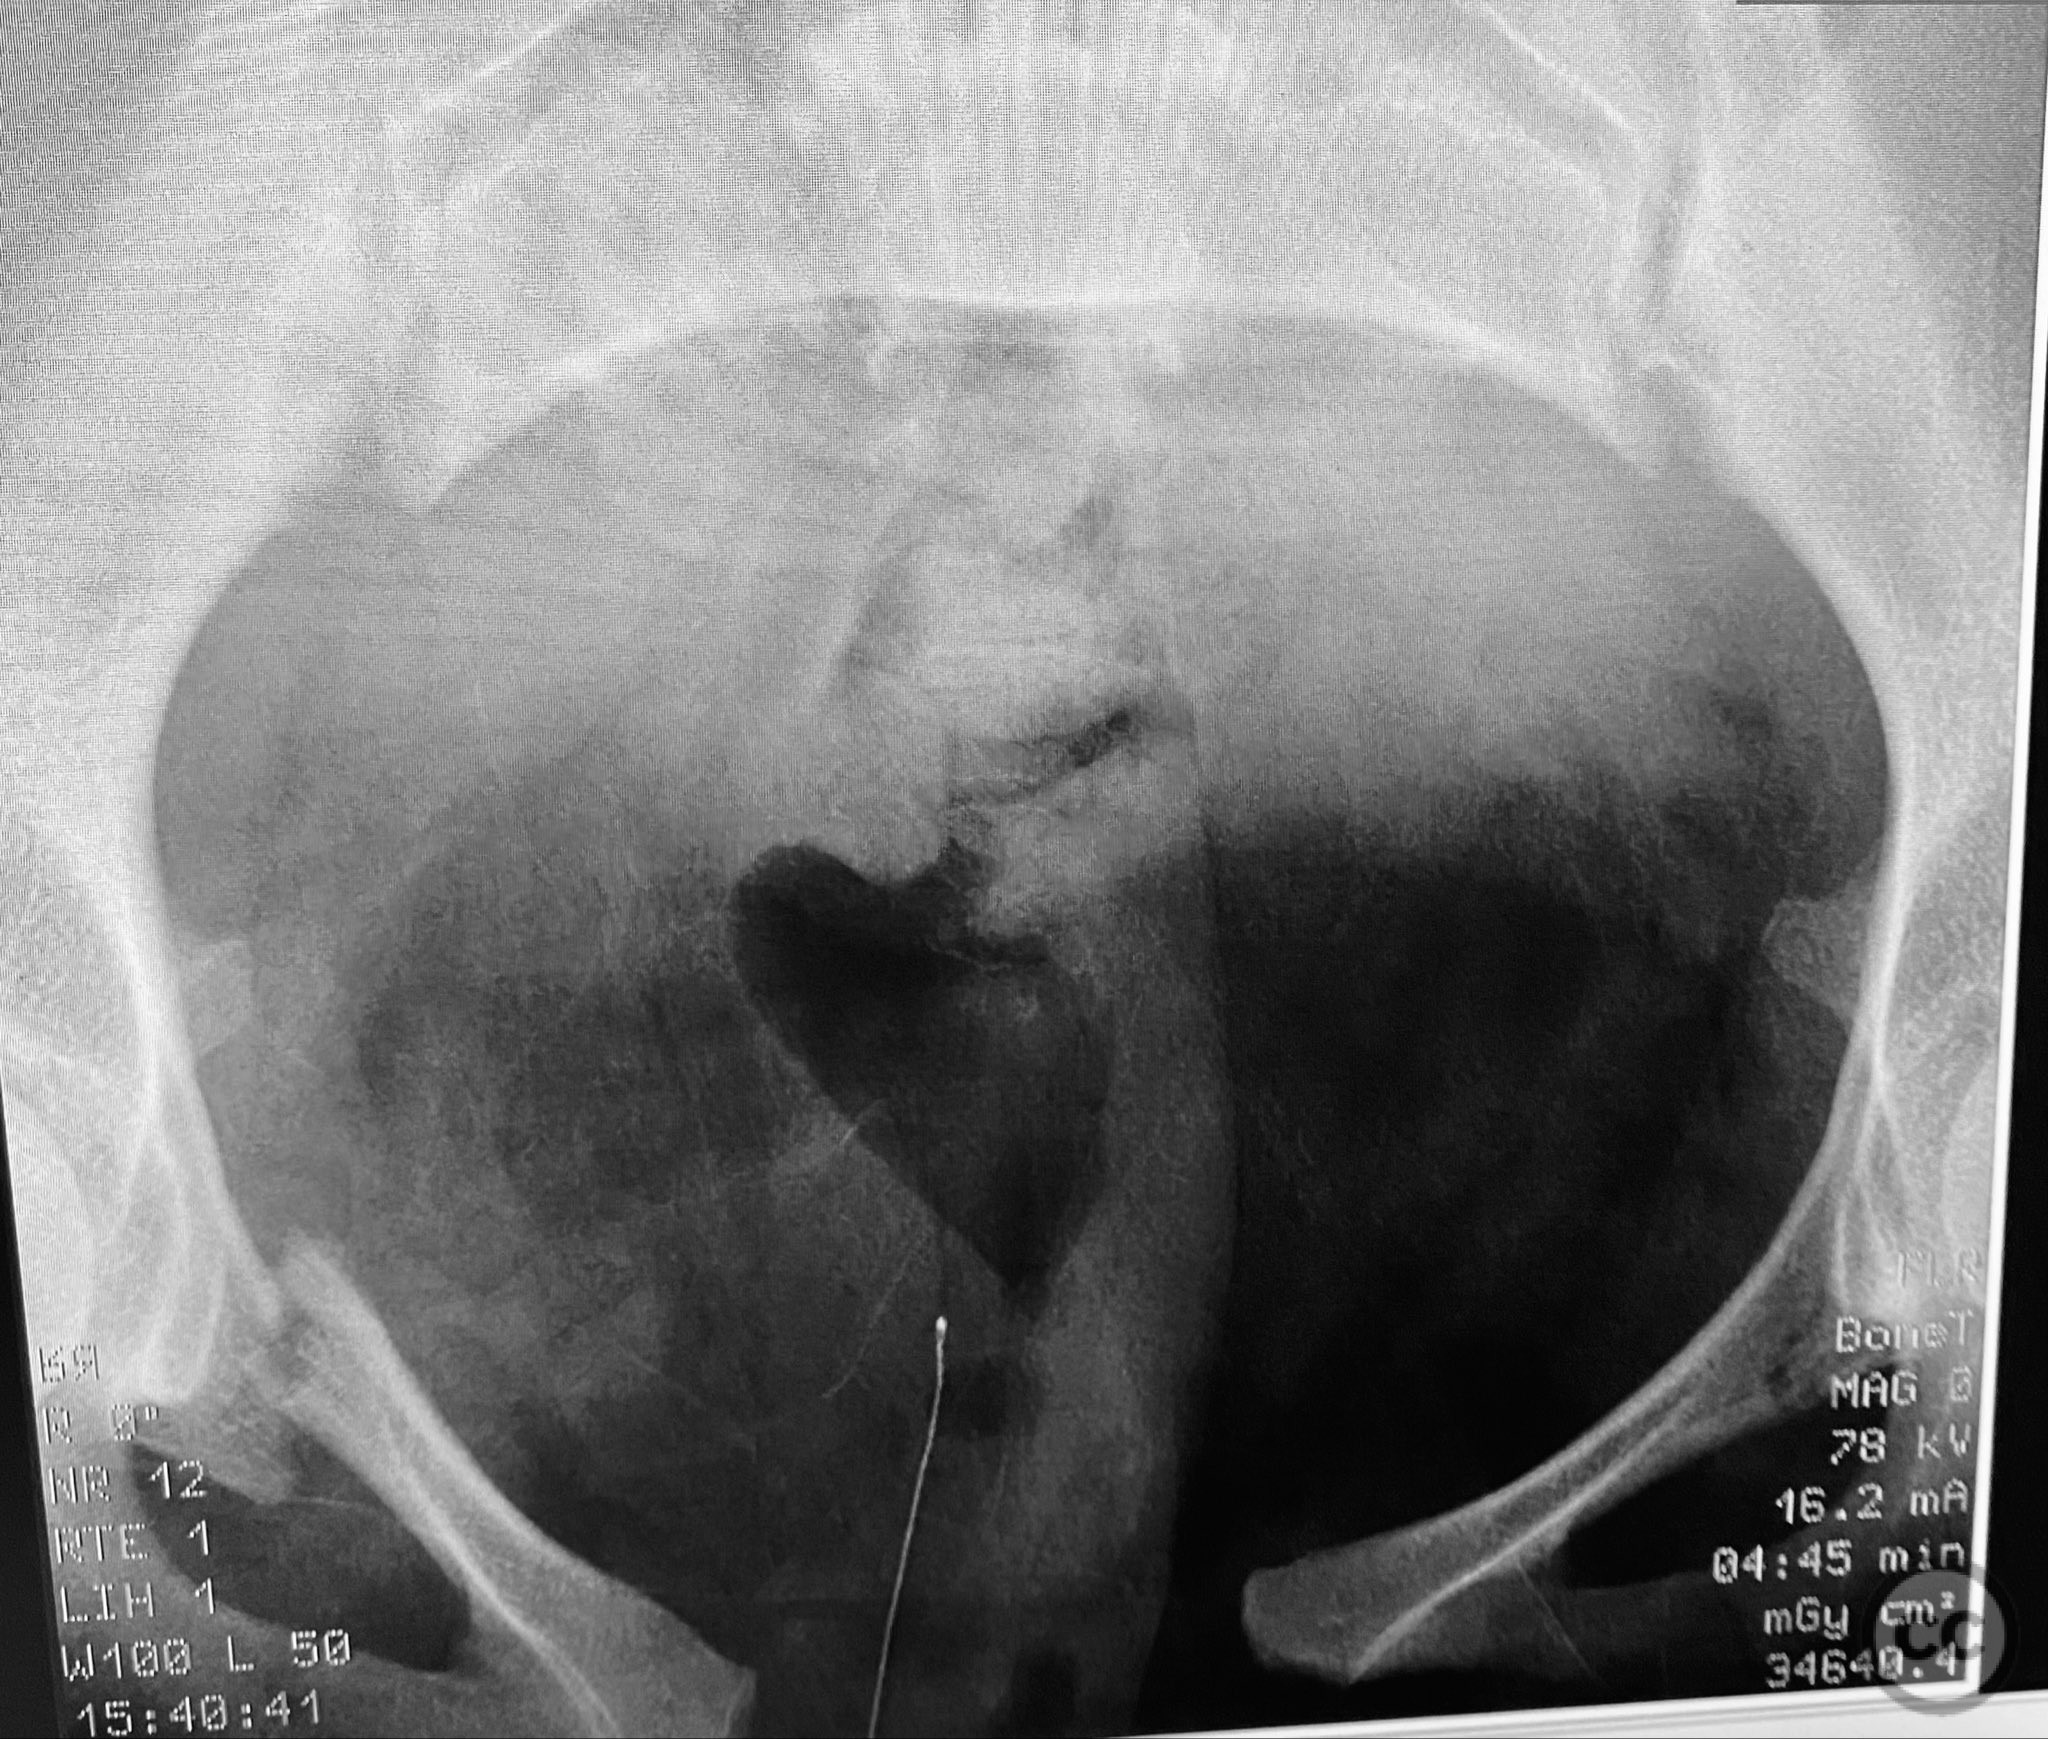

Clinical and radiological findings:  A young adult female sustained a high-energy pelvic injury following a motorcycle crash. She was hemodynamically stable on presentation, with normal neurovascular examination and no evidence of genitourinary, vaginal, or rectal injury. She reported pain localized to both anterior and posterior pelvic regions. Initial plain radiographs (with and without pelvic binder) demonstrated multiple anterior ring fractures and dislocations. The binder images obscured the full extent of injury. Further intraoperative fluoroscopic imaging (AP, inlet, and with lower extremities in "lotus" position) revealed bilateral sacroiliac (SI) joint disruptions (right greater than left), bilateral superior/inferior pubic ramus fractures (right greater than left), and symphyseal diastasis. Notably, the right pubic ramus demonstrated excessive curvature, complicating potential percutaneous screw fixation. AO/OTA classification: 61-C1.3 (bilateral complete disruption of the posterior arch with associated anterior ring injury). Young-Burgess classification: APC III.

Patient positioning:  The patient was positioned supine on a radiolucent operating table under general anesthesia. For intraoperative assessment, the lower extremities were placed in a "lotus" position to enhance visualization of pelvic ring injuries under fluoroscopy.

Intraoperative fluoroscopy with AP and inlet views, as well as dynamic positioning of the lower extremities, was critical in fully delineating the extent of injury, which had been underestimated on preoperative imaging due to binder application. The excessively curved morphology of the right pubic ramus precluded safe or effective straight screw fixation; therefore, ORIF with a contoured plate was performed using intrapelvic exposure for optimal fit and stability. Indirect closed reduction of the SI joints was accepted, followed by percutaneous trans-sacral screw fixation under fluoroscopic guidance. This case highlights the necessity of thorough intraoperative assessment for occult or underestimated injury patterns in complex pelvic trauma, particularly when initial imaging is performed with a pelvic binder in situ.